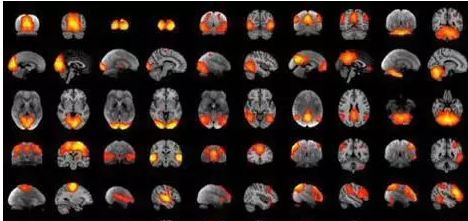

在脑科学还没那么发达的时候,科学家研究大脑功能的方法之一,就是研究脑损伤患者的大脑。根据损伤的大脑位置以及他们所出现的障碍,来推断出脑部某个部位的认知功能。而在脑科学日渐发达的现在,随着PET(正电子发射断层扫描成像)和fMRI(功能性磁共振) 等技术的出现,我们可以逐渐揭开大脑的神秘面纱。

fMRI图像全角度显示脑部活动情况

学者们都在致力于找出最能代表与产生意识有关的神经元组合(NCC),也就是与特定意识经验吻合的脑部活性。有观点认为,每一个意识经验,都是特定脑区里的一群独特神经元以特定方式产生的活性所造成的。连结脑背与前面皮质的锥体神经元联盟以独特方式活化,不同联盟的活化代表了感官的不同刺激。

也有观点认为每一个意识经验,都是许多脑区域神经元同步活化而成的和谐组合,然后消散。跨脑区神经元同步活化(绿色),直到第二个刺激形成不同的组合(黄色)。各种不同组合时聚时散,整合身体输入的讯息。在电刺激大鼠脑中视丘(下)之后的0.35秒,组合在大脑皮质中形成(a,b)、达到颠峰(c),然后消散(d)。